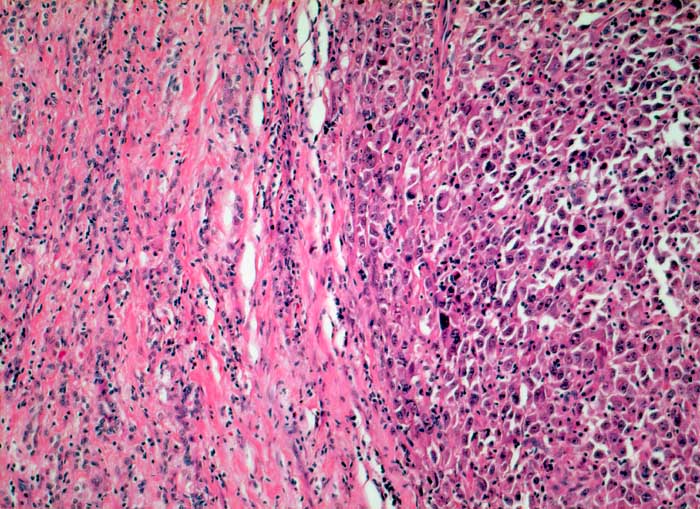

Anaplastisches Schilddrüsenkarzinom

Anaplastischer solider Tumorknoten mit bizarren grossen Tumorzellen.